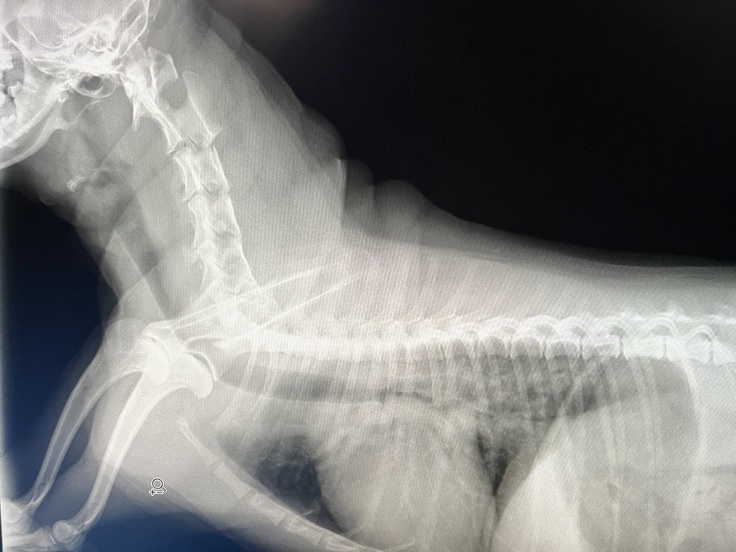

〔7月29日 肺水腫を起こしているレントゲン〕

左7月29日心臓が大きくなっている状態

右8月5日獣医師による処置により改善